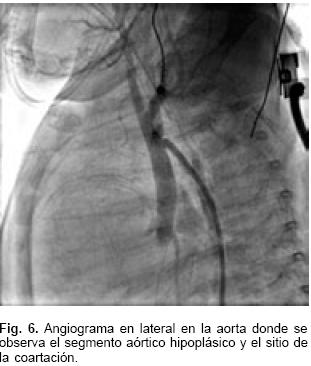

El ecocardiograma mostró foramen oval permeable, conexión atrioventricular concordante y relación atrioventricular discordante, posición superior del ventrículo derecho e inferior del izquierdo (Fig. 3); doble salida del ventrículo derecho con vasos ligeramente cruzados; estenosis subaórtica por desviación del septum infundibular; comunicación interventricular infundibular, hipoplasia del arco aórtico con una zona de coartación de tipo tubular muy estrecha y con gradiente 65 mm Hg. La presión sistólica de la arteria pulmonar (PSAP) era de 90 mm Hg. La arteria pulmonar se observó muy dilatada con datos de probable conducto arterioso persistente.

El estudio hemodinámico corroboró los diagnósticos y demostró que las presiones en ambos ventrículos, la arterial pulmonar y de la aorta eran las mismas; la presión sistólica sistémica fue de 50 mm Hg. Se evidenció una comunicación interventricular trabecular pequeña. El gradiente entre el arco aórtico y la aorta descendente fue de 17 mm Hg, con coartación aórtica yuxtaductal e hipoplasia importante del istmo aórtico y de la porción horizontal del arco; se confirmó la permeabilidad del conducto arterioso (Figs. 4, 5 y 6). La resonancia magnética nuclear hizo más relevantes las características anatómicas, para presentar el caso al Servicio de Cirugía (Fig 7).